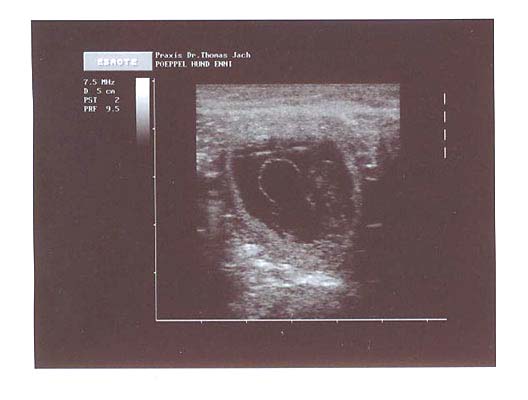

54. Tag: Eine weitere

Woche ist seit dem letzten Tagebucheintrag vergangen. Ennis Bauch

wächst nach wie vor weiter und sie bekommt ihr Fressen

mittlerweile in mehreren, kleineren Portionen. Wir haben ihre

Wurfkiste nun auch so eingerichtet, wie sie bis zur Geburt

bleiben soll. Nach wie vor gehen wir gerade bei dem schönen

Wetter noch durch den Wald, was Enni sehr freut. Nach solch

einer Runde ist sie dann aber auch fix und fertig. Ab nächste

Woche werden wir anfangen zweimal täglich ihre Temperatur zu

messen und ab Dienstag oder Mittwoch könnte die Geburt

theoretisch auch beginnen.